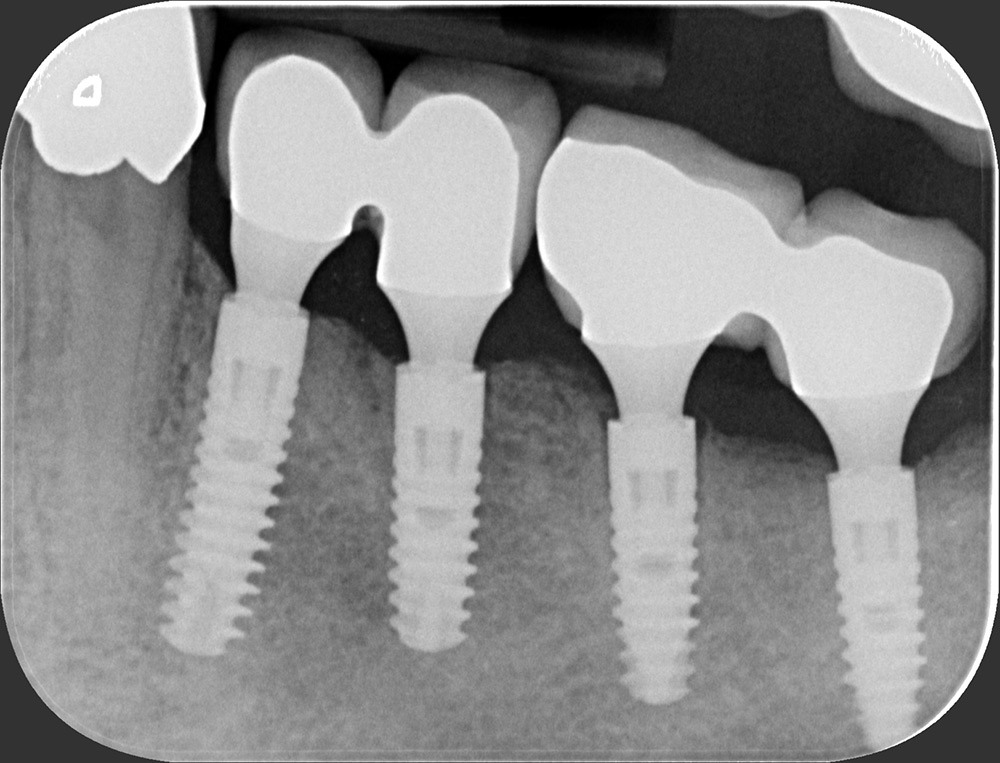

Zahnarztpraxis Heise, Röntgenbild einer Implantat-Versorgung

Röntgenbild einer Implantat-Versorgung